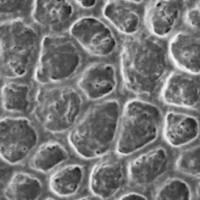

药物对家兔浦肯野纤维动作电位的作用

文献和实验,细胞才对刺激发生可扩布的动作电位。从除极开始到这以前的一段时间即为有效不应期(effective refractory period,ERP),它反映快钠通道恢复有效开放所需的最短时间。其时间长短一般与APD的长短变化相应,但程度可有不同。一个APD中,ERP数值大,就意味着心肌不起反应的时间延长,不易发生快速型心律失常。 图22-1 浦肯野纤维的快反应与慢反应电活动 A快反应 B慢反应 二、心律失常发生的电生理学机制 心律失常可由

佚名 一、正常心肌电生理 (一)心肌细胞膜电位 心肌细胞的静息膜电位,膜内负于膜外约-90mV,处于极化状态。心肌细胞兴奋时,发生除极和复极,形成动作电位。它分为5个时相,0相为除极,是Na + 快速内流所致。1相为快速复极初期,由K + 短暂外流所致。2相平台期,缓慢复极,由Ca